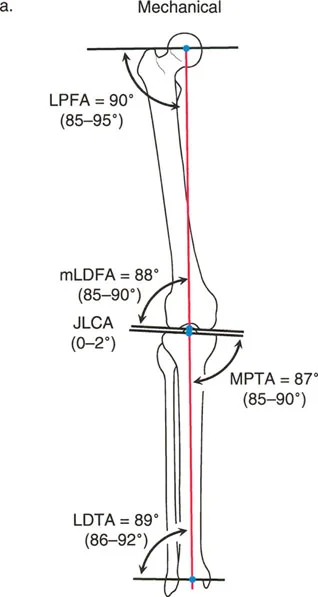

The nomenclature follows a strict formula: [Axis] + [Medial/Lateral] + [Proximal/Distal] + [Bone] + Angle.

- Axis: 'm' for mechanical, 'a' for anatomic.

- Side: 'M' for medial, 'L' for lateral, 'A' for anterior, 'P' for posterior.

- Location: 'P' for proximal, 'D' for distal.

- Bone: 'F' for femur, 'T' for tibia.

- Angle: Always ends with 'A' for Angle.

For example, mLDFA stands for the mechanical Lateral Distal Femoral Angle.

Frontal Plane Femoral Angles

- mLDFA (mechanical Lateral Distal Femoral Angle): The angle between the mechanical axis of the femur and the distal femoral joint line on the lateral side.

- Normal Value: 87° (Range: 85° - 90°)

- aLDFA (anatomic Lateral Distal Femoral Angle): The angle between the anatomic axis of the femur and the distal femoral joint line on the lateral side.

- Normal Value: 81° (Range: 79° - 83°)

- mLPFA (mechanical Lateral Proximal Femoral Angle): The angle between the mechanical axis of the femur and the proximal femoral joint line.

- Normal Value: 90° (Range: 85° - 95°)

Frontal Plane Tibial Angles

Because the mechanical and anatomic axes of the tibia are parallel, we generally refer only to the mechanical angles, which apply to both axes.

- MPTA (Medial Proximal Tibial Angle): The angle between the mechanical/anatomic axis of the tibia and the proximal tibial joint line on the medial side.

- Normal Value: 87° (Range: 85° - 90°)

- LDTA (Lateral Distal Tibial Angle): The angle between the mechanical/anatomic axis of the tibia and the distal tibial joint line on the lateral side.

- Normal Value: 89° (Range: 86° - 92°)

Joint Line Congruency Angle JLCA

The Joint Line Congruency Angle (JLCA) is measured between the joint line of the distal femur and the joint line of the proximal tibia. It evaluates the soft tissue envelope (ligamentous laxity) and cartilage wear of the knee.

* Normal Value: 0° to 2° (joint lines are nearly parallel).

* Clinical Significance: A JLCA greater than 2° indicates intra-articular deformity, such as collateral ligament laxity or asymmetric cartilage loss. If a patient has a varus deformity with a large JLCA, correcting only the bony deformity without addressing the ligamentous laxity will result in under-correction.

Sagittal Plane Angles

Sagittal plane analysis is equally critical, particularly for preventing recurvatum or procurvatum deformities that alter gait kinematics.

- aPDFA (anatomic Posterior Distal Femoral Angle): 83° (Range: 79° - 87°)

- PPTA (Posterior Proximal Tibial Angle): 81° (Range: 77° - 84°). This represents the natural posterior slope of the tibial plateau.

- ADTA (Anterior Distal Tibial Angle): 80° (Range: 78° - 82°).